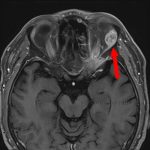

症例 '25年11月

No.

696

※ 画像をクリックすると拡大表示します。症例No.は平成29年から起算しています。

年_番号

手術年月

患者年齢

’25_98

'25年11月

70代

病名

術式

備考

眼窩腫瘍

頭蓋内腫瘍摘出術

断層撮影

手術前

1